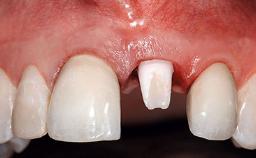

Replacement of a Compromised Upper Right Central Incisor: Hard- and Soft-tissue Augmentation, Late Placement of an RC Bone Level Implant

A 36-year-old male patient with a compromised maxillary central incisor was referred by his general dentist for consultation. The patient’s chief complaints were the gradual debonding of a temporary crown on the right central incisor and unsatisfactory esthetics due to an increasing diastema between the right central and lateral incisors. The patient reported a traumatic event some years previously, when a crown had been placed after root-canal treatment. The referring dentist wanted to provide a new crown restoration, but was concerned about the condition of the residual root. Anamnesis was negative for any other dental or periodontal pathology in the remaining dentition. The patient reported taking no medications: He was a smoker (10 to 15 cigs/day) and had realistic esthetic expectations.

Soft Tissue Anatomy Intact Defective

Bone Volume Horizontally and vertically sufficient Horizontally deficient Deficient vertically or deficient vertically AND horizontally

Soft Tissue Contour and Volume Slightly compromised